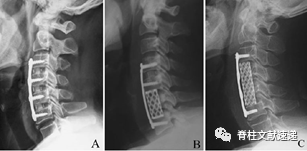

多节段ACDF,包括C5P在内等并发症发生率大大降低;

连续长节段椎体次全切除并发症多,应慎重选择。